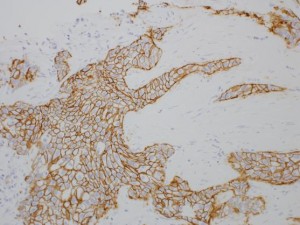

病理医が患者様の組織や細胞から作られた病理標本を詳細に観察し、顕微鏡診断を行います。病気の原因や信仰を読み解く病理学の知識に基づき、正確な診断で治療方針決定に貢献します。

病理診断科では、病理診断を行う医師(病理医)が、病理標本を観察して診断を行います。

病理標本とは、患者さんの身体から手術や検査などで採取された組織や細胞であり、そこに隠れている病気を顕微鏡で詳細に観察し、病理診断を下します。顕微鏡下に広がる組織や細胞像から病気であることを同定するためには、病理学の知識が必要です。病理学とは、病気の理屈を考える学問で、なぜ病気になるのか? 病気にかかった人はどのような症状を出し、その後どうなっていくのか?などを読み解く学問です。

病理診断とは患者さんの身体から提供された病変を顕微鏡などで観察し、病気の性格を見分けて臨床医に診断報告することです。病気になると、組織や細胞の構築が崩れ、それを修復しようとする体細胞の反応が現れてきます。正確に病理診断を行うためには、組織や細胞の形態変化や体細胞が織りなす種々の反応を捉える知識が必要です。さらに、CT、MRI、エコー検査などの画像診断結果を理解することは勿論ですが、患者さんの苦しみを理解し総合的に正しい病態を把握することが大切です。